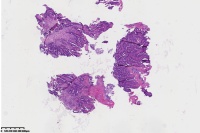

中分化腺癌?

直肠占位

腺癌(低一中 分化)

中分化腺癌